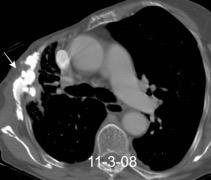

40. EMPIEMA PLEURAL. ORIGEN HEPÁTICO

Colecciones “inflamatorias” abdominales llegan al tórax vía el hiato esofágico o por vía transdiafragmática

Afectación transdiafragmática: 5,6-43,7% de quistes hepáticos. “Área desnuda” del hígado.

Panda A et al. “Straddling Across Boundaries”. Thoracoabdominal Lesions: Spectrum and Pattern Approach. Curr Probl Diagn Radiol. 2015 Área desnuda. El hígado en contacto directo con el tendón central del diafragma. Contiene el hiato de VCI.